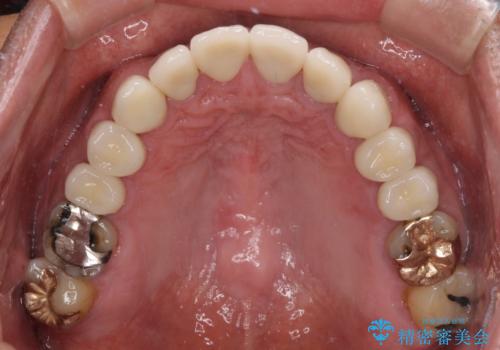

当初は前歯6歯をオールセラミッククラウンで補綴する予定でしたが、前歯が綺麗に仕上がったことで、奥歯まで延長して補綴することとしました。

黄ばんだ前歯や白すぎたクラウン、プラスチックの継ぎ接ぎなどを全てオールセラミッククラウンの統一感のある前歯に仕上げました。